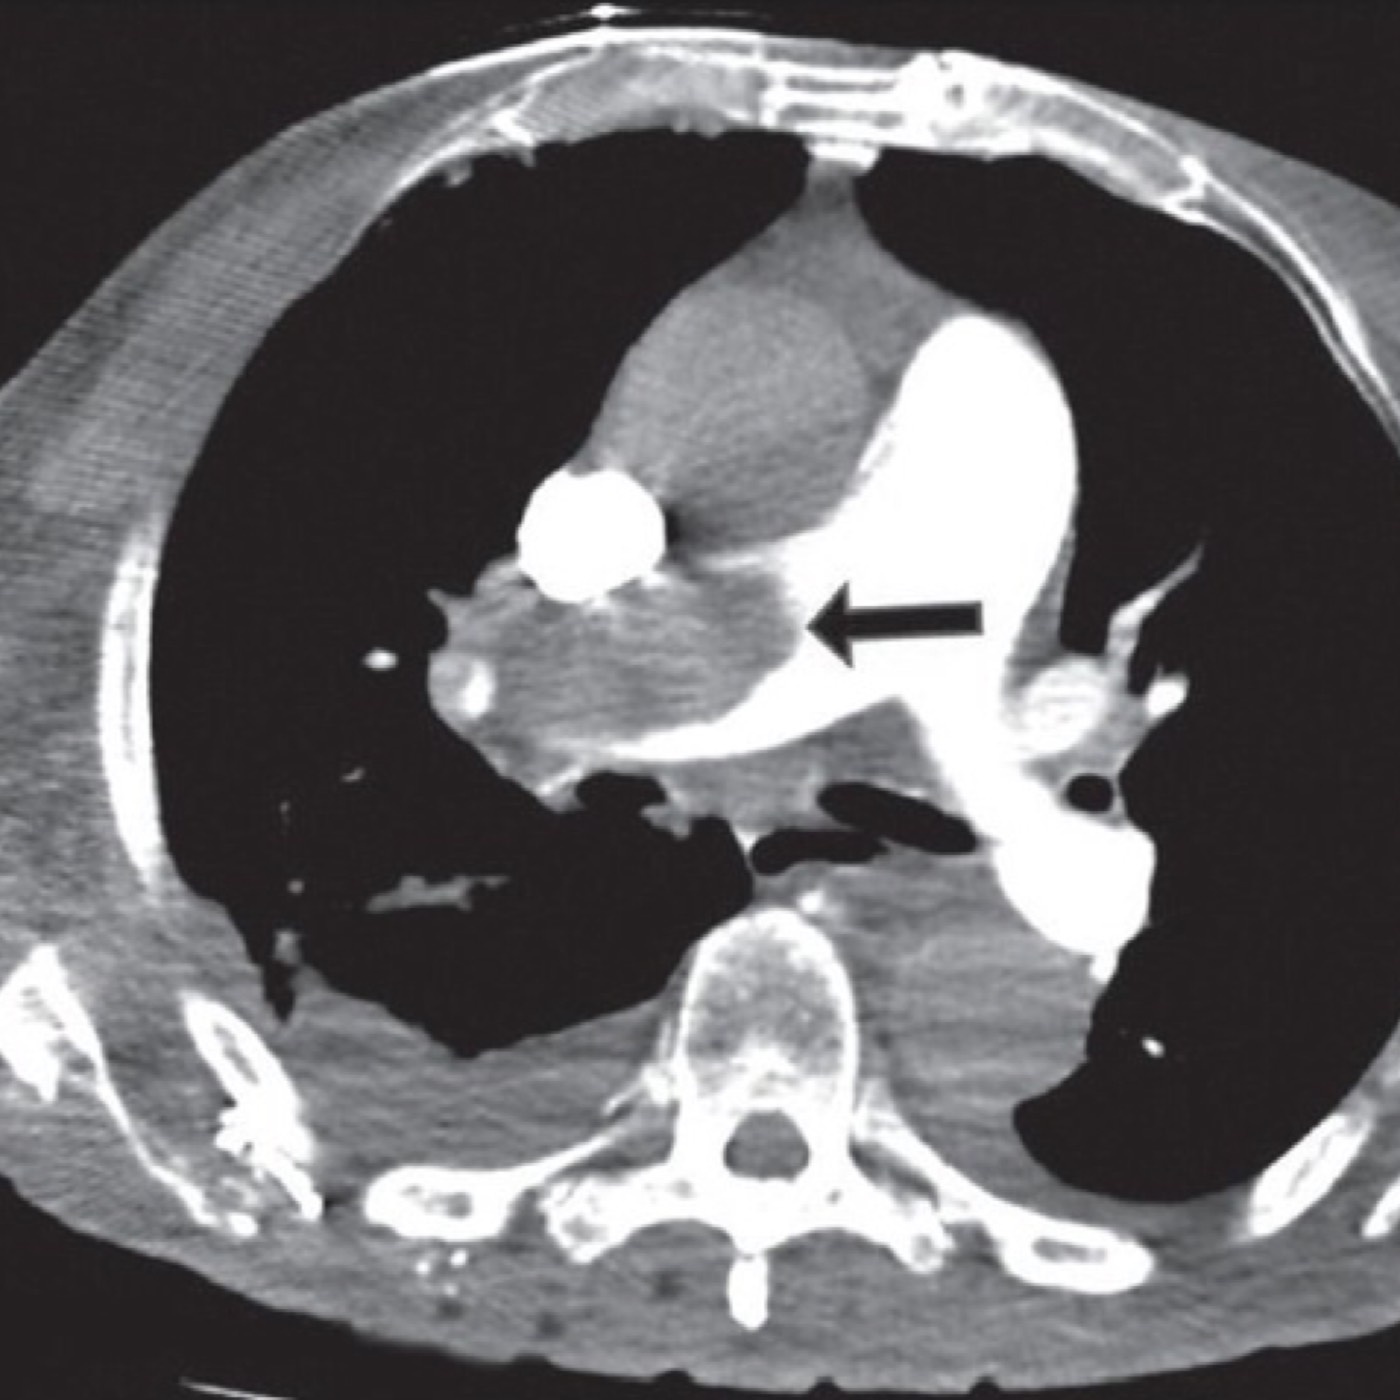

Contributor: Alec Coston, MD Case Report Summary: A 17-year-old female involved in a motor vehicle collision presented to a rural emergency facility via personally operated vehicle. During workup and initial CT scan, the patient began rapidly decompensating with CT revealing a 1.5cm epidural hematoma with 7mm of midline shift. The patient went from being able to walk and talk to being obtunded with a blown left pupil and unresponsive. Following intubation, the patient was being prepared for transport but potential delays required immediate emergency evacuation of the hematoma via a Burr Hole. A traditional Burr Drill was not immediately available at the facility, so an improvised Burr Drill using an Intraosseous (IO) drill was used. 35mL of blood was removed from the hematoma and the patient immediately improved from a GCS of 3 to GCS of 8. The patient was transferred to a higher level of care facility, extubated the following day, and made a full neurological recovery. Educational Pearls: What is an epidural hematoma? An epidural hematoma is a collection of blood between the dura mater (outermost layer of the meninges) and the skull, whereas a subdural hematoma is a collection of blood between the dura mater and arachnoid mater. Both can be life threatening depending on location and size. Epidural hematomas tend to be arterial, and are typically secondary to trauma and can rapidly expand, but with timely recognition and evacuation of the bleed, favorable outcomes are often possible. What are typical intracranial pressures and at what levels do they become pathologic? Typical intracranial pressure (ICP) varies by age, but past infancy and early childhood, adolescents and adults have a value typically between 8-15mmHg. Values exceeding 20mmHg become pathologic and rise exponentially with increased volume. Initial symptoms may include headache, nausea, and vomiting, but with increased pressures may progress to more life threatening symptoms such as loss of consciousness, cranial nerve palsies, pupillary constriction or dilation (sign of herniation), and respiratory irregularities. What is the takeaway in timing of epidural hematomas? Older studies show that evacuation of a hematoma with lateralizing features before the two hour mark of coma symptom onset is correlated with decreased mortality (ranging from 15-17%), but beyond 2 hours the mortality increases to well over 50%. Though mortality statistics have grown more variable, early targeted evacuation of epidural hematomas still remains critical for improved patient outcomes. In austere conditions with limited resources, improvisation with interosseous drills and needles can improve patient outcomes and achieve the target therapy for epidural hematomas. References Haselsberger K, Pucher R, Auer LM. Prognosis after acute subdural or epidural haemorrhage. Acta Neurochir (Wien). 1988;90(3-4):111-116. doi:10.1007/BF01560563 Hawryluk GWJ, Nielson JL, Huie JR, et al. Analysis of Normal High-Frequency Intracranial Pressure Values and Treatment Threshold in Neurocritical Care Patients: Insights into Normal Values and a Potential Treatment Threshold. JAMA Neurol. 2020;77(9):1150-1158. doi:10.1001/jamaneurol.2020.1310 Pisică D, Volovici V, Yue JK, et al. Clinical and Imaging Characteristics, Care Pathways, and Outcomes of Traumatic Epidural Hematomas: A Collaborative European NeuroTrauma Effectiveness Research in Traumatic Brain Injury Study. Neurosurgery. 2024;95(5):986-999. doi:10.1227/neu.0000000000002982 Summarized by Dan Orbidan, OMS2 | Edited by Dan Orbidan and Jorge Chalit, OMS4 Donate: https://emergencymedicalminute.org/donate/